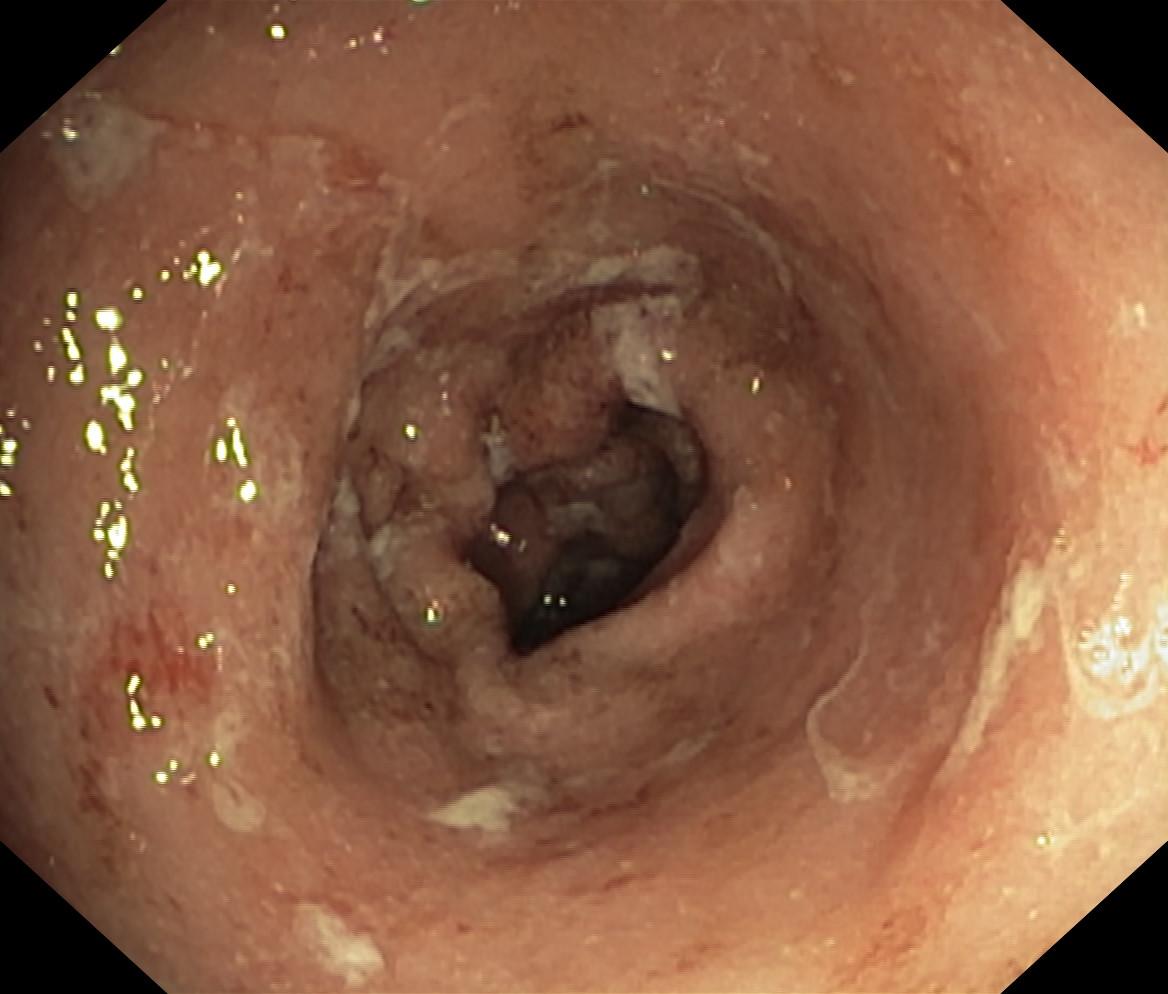

Obrazy endoskopowe

Nowotwory przewodu pokarmowego